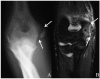

Context: As the intensity of youth participation in athletic activities continues to rise, the number of overuse injuries has also increased. A subset of overuse injuries involves the physis, which is extremely susceptible to injury. This paper aims to review the utility of the various imaging modalities in the diagnosis and management of physeal injuries in the skeletally immature population.

Results: Three major imaging modalities (radiographs, computed tomography, and magnetic resonance imaging) complement each other in the evaluation of pediatric patients with overuse injuries. However, magnetic resonance imaging is the only modality that offers direct visualization of the physis, and it also offers the best soft tissue contrast for evaluating the other periarticular structures for concomitant injury.

Conclusion: Imaging has an important role in the diagnosis of physeal injuries, and the information it provides has a tremendous impact on the subsequent management of these patients.